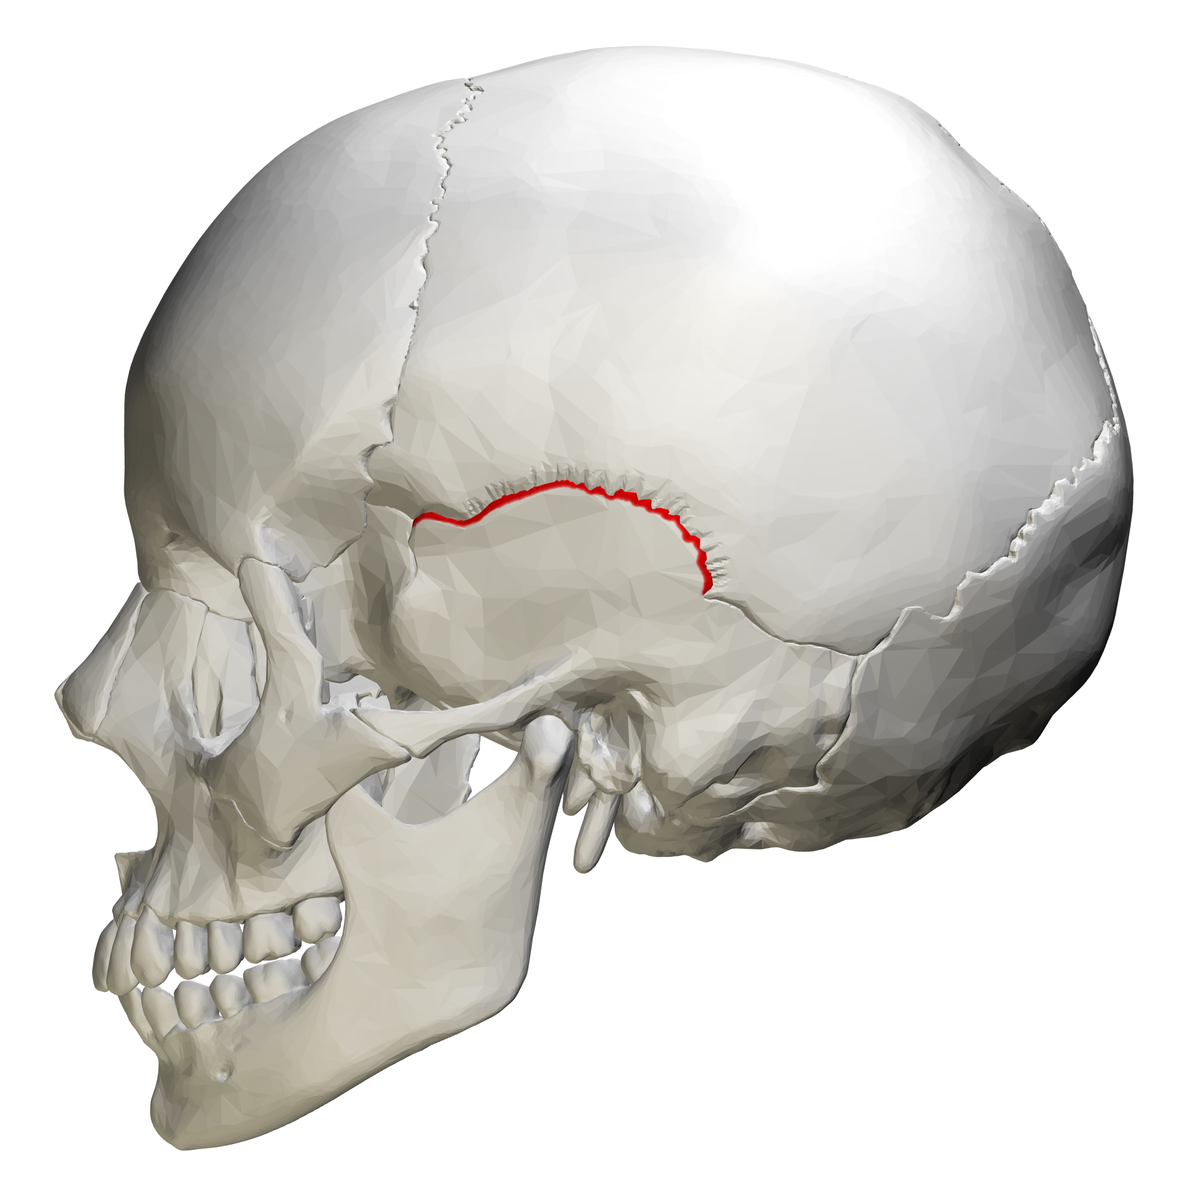

What are skull sutures?

Interlocking immovable joints of the skull

What suture is this?

Squamous Suture

What do sutures tell you about the skull?

It shows that the skull is made up of more than one bone